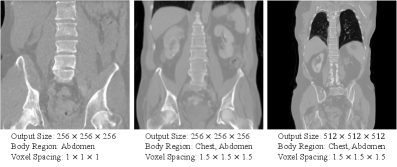

The datasets for developing the Diffusion model used in MAISI comprise 10,277 CT volumes from 24 distinct datasets, encompassing various body regions and disease patterns. Table S2 provides a summary of the number of volumes for each dataset. For compatibility with the shape requirement of the U-shape network, we resample the dimensions of volumes to multiples of 128. Fig. S1 visualizes the characteristics and spatial complexity of the data involved in training the diffusion model.

Refer to caption

Figure S1: The characteristics of the datasets utilized for the MAISI Diffusion Model are detailed through two subplots. Subplot (a) illustrates the volume dimensions of the datasets, providing insight into the variability and range of sizes used in the training data. Subplot (b) presents the voxel spacing in millimeters for each data point, emphasizing the spatial configuration within the CT scans. Notably, in CT imaging, the X and Y directions typically share identical dimensions and spacing, so they are represented on a single axis in both subplots.